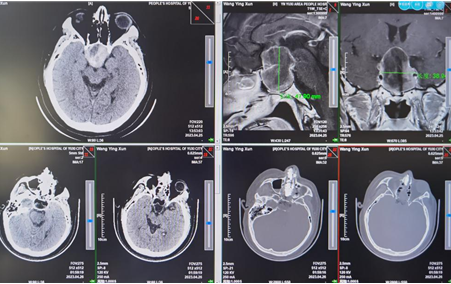

神经外科接诊团队立即对其情况进行了检查,并根据患者实际病情为其打开生命救治绿色通道。经过检查确诊,患者是因颅内巨大垂体腺瘤并出血,压迫脑神经,导致双眼失明。

当晚10点半,肖顺武教授到位,神经外科团队为患者实施了经鼻蝶入路全神经内镜下微创手术切除巨大垂体腺瘤,及时行视神经减压手术。术后第二天,患者左眼鼻侧已经有了光感,一周后左眼前距离20cm处能看清手指,术后视力较术前有改善;到患者出院时,患者视力逐步提升,已能完成基本生活自理,并独立行走,患者和家属对此次诊治表示肯定。

(图:垂体腺瘤手术前后影像学资料对比)